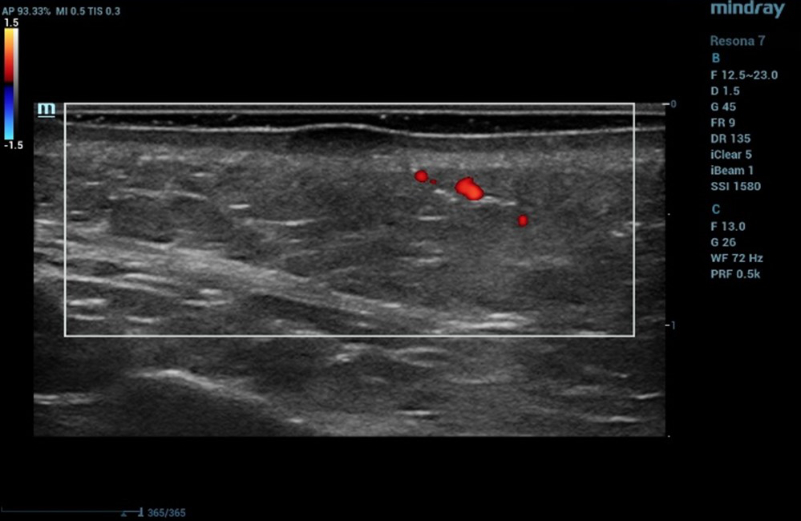

Ultrasound examination of the nevus was performed on the Resona 7 ultrasound machine (Mindray, China) using the high frequency linear transducer L20-5U (max frequency 23 MHz). When the transducer was placed in the projection of the visible nevus of the right zygomatic region of the face, the derma was locally thickened to 2.4 mm due to a hypoechogenic mass located under the epidermis and slightly elevated, spreading in depth to all layers of the dermis with clear rough boundary of heterogeneous echogenicity, without hyperechogenic sports, giving a weak acoustic darkening of the echo signal (Figure 2). Blood flow is not registered inside the nevus in the Color Doppler mode (Figure 3).

Ultrasound examination of the nevus in B mode

Figure 2. Ultrasound examination of the nevus in B mode

Ultrasound examination of the nevus in Color Doppler mode

Figure 3. Ultrasound examination of the nevus in Color Doppler mode

Such ultrasound signs are characteristic of compound nevus [2]. A pronounced subcutaneous low-echo band (SLEB) attracts attention (0.9 mm – 50% of the total thickness of the dermis – 1.7 mm), which is the ultrasound sign of facial skin photodamage [3].